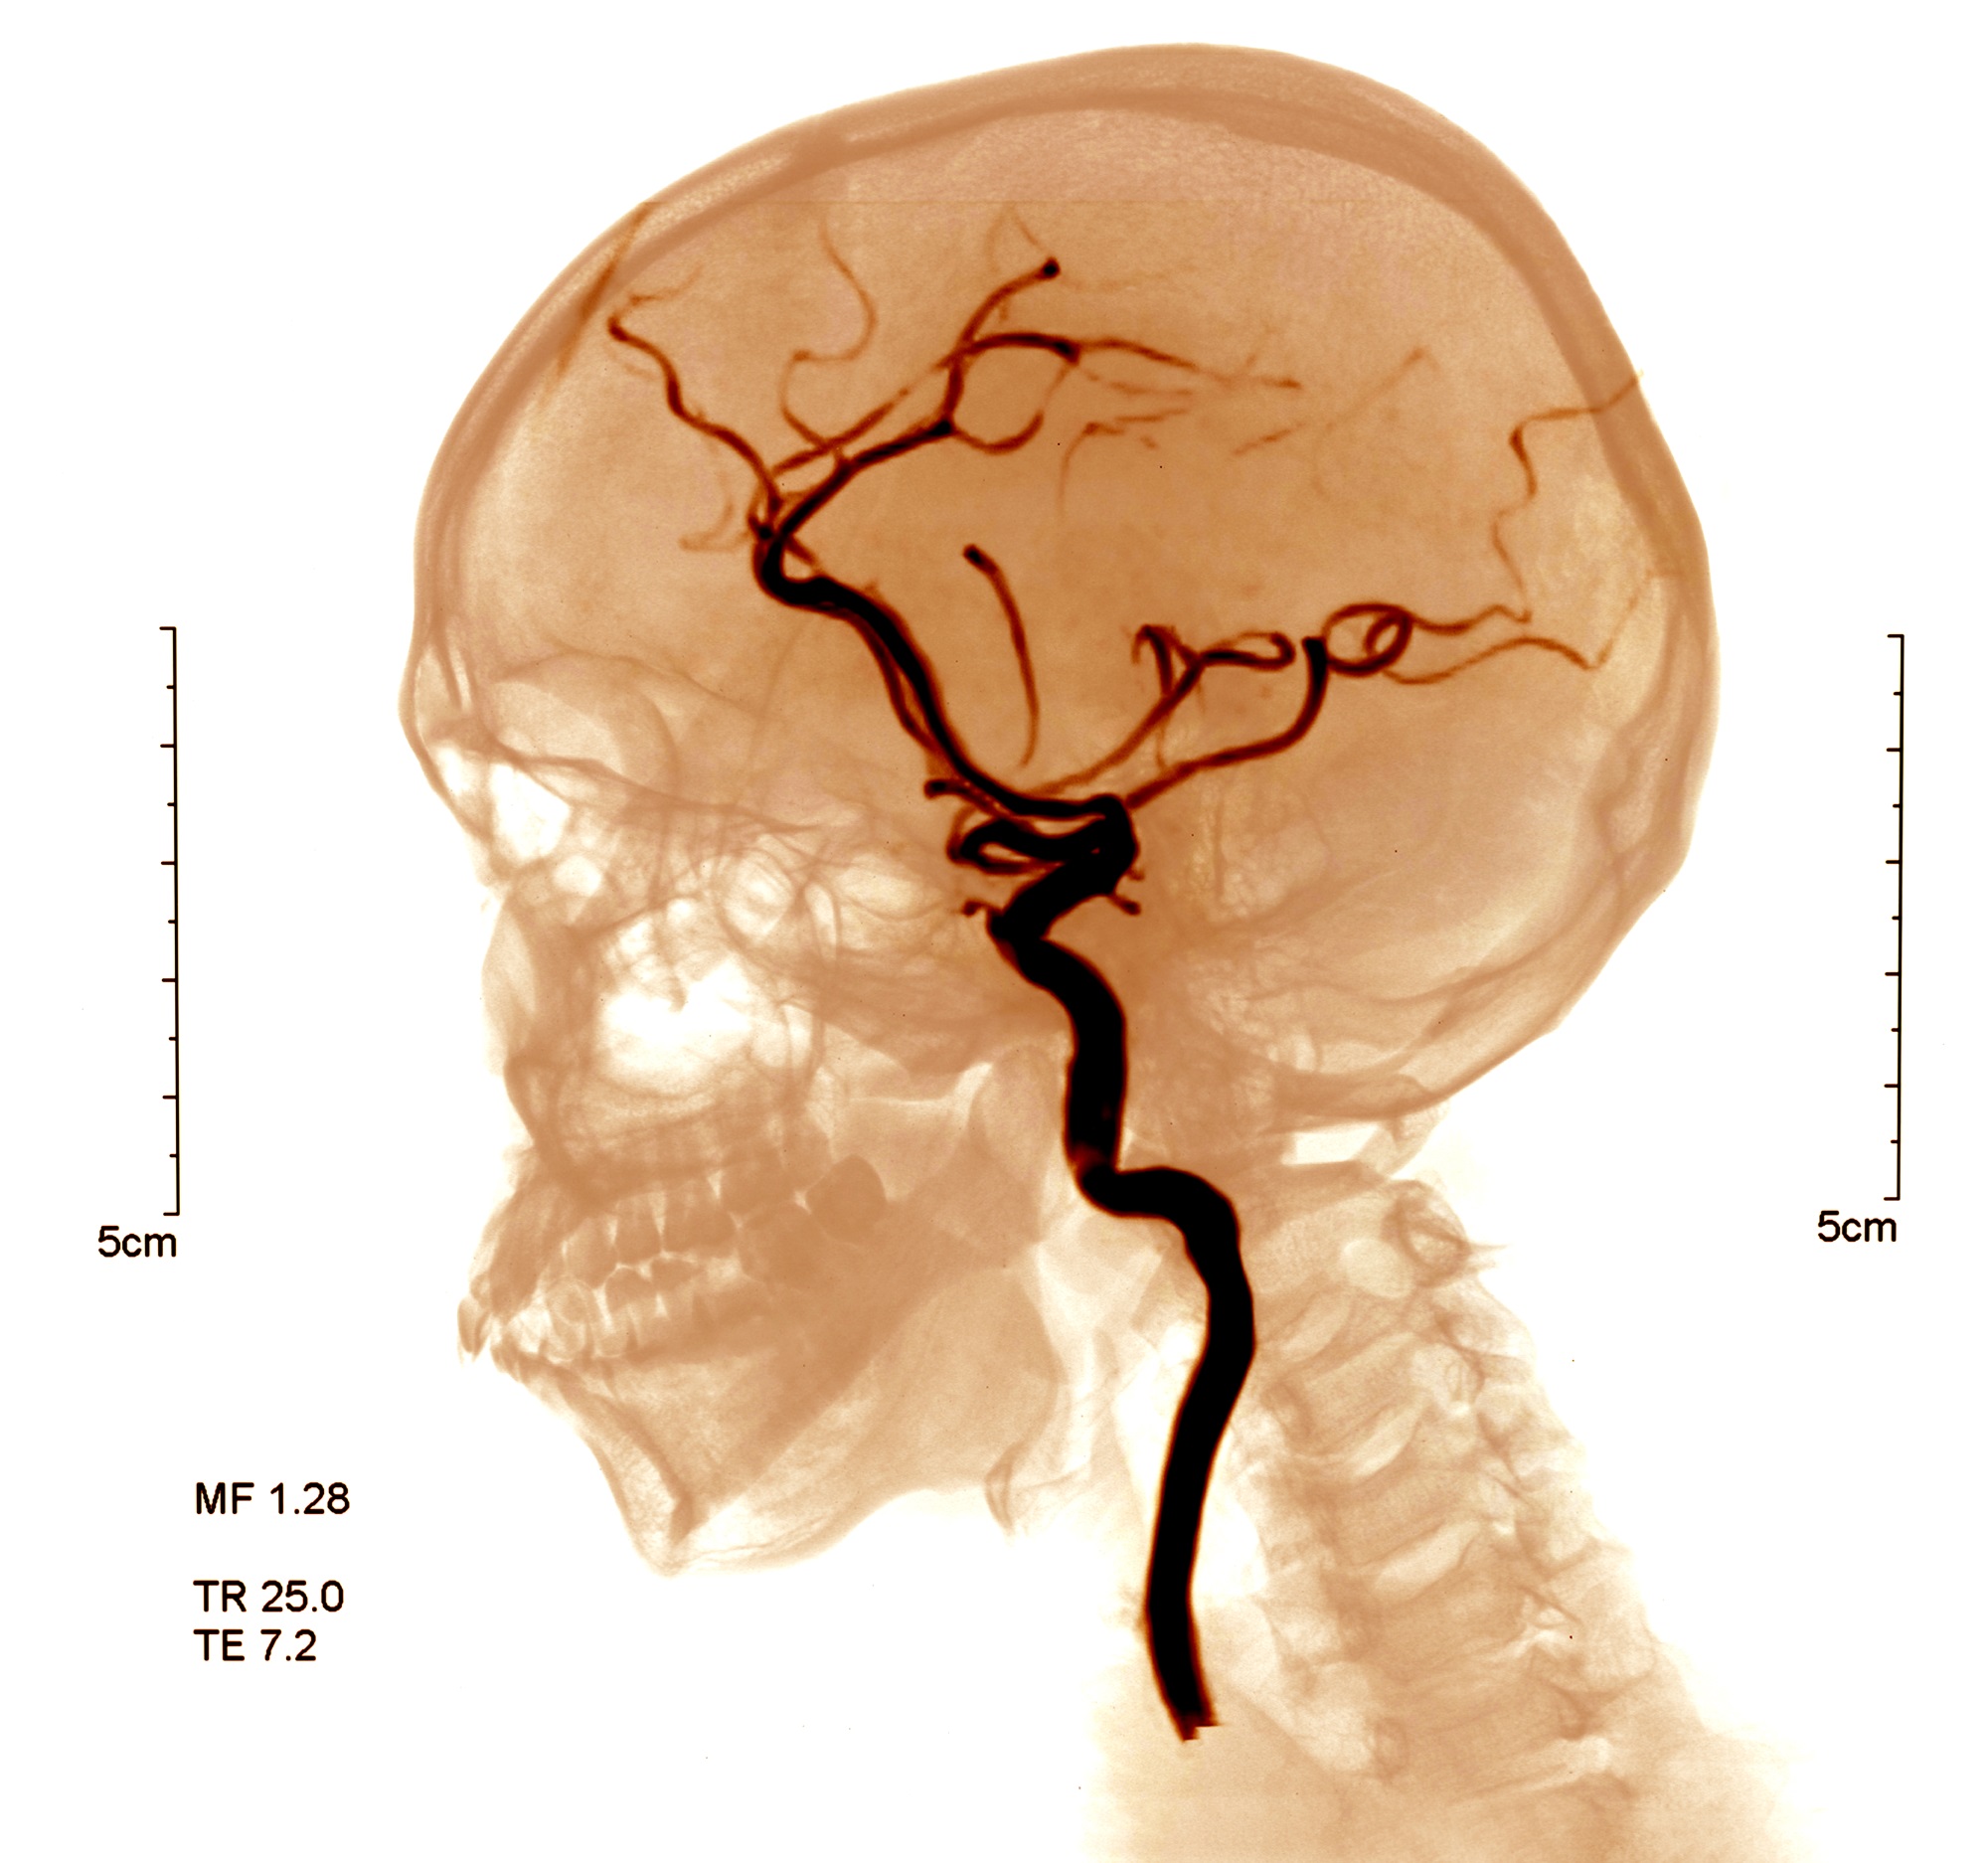

뇌졸중이란 뇌에 혈액을 공급하는 혈관이 차단되거나 파열되어 뇌 손상 및 신체장애를 일으키는 뇌혈관 질환을 뜻합니다.

'중풍' 또는 '뇌혈관 질환'이라고 불리는 것이 바로 뇌졸중입니다.

뇌경색과 뇌출혈은 뇌졸중의 종류로 뇌졸중 안에 뇌경색, 뇌출혈이 포함된다고 볼 수 있습니다.